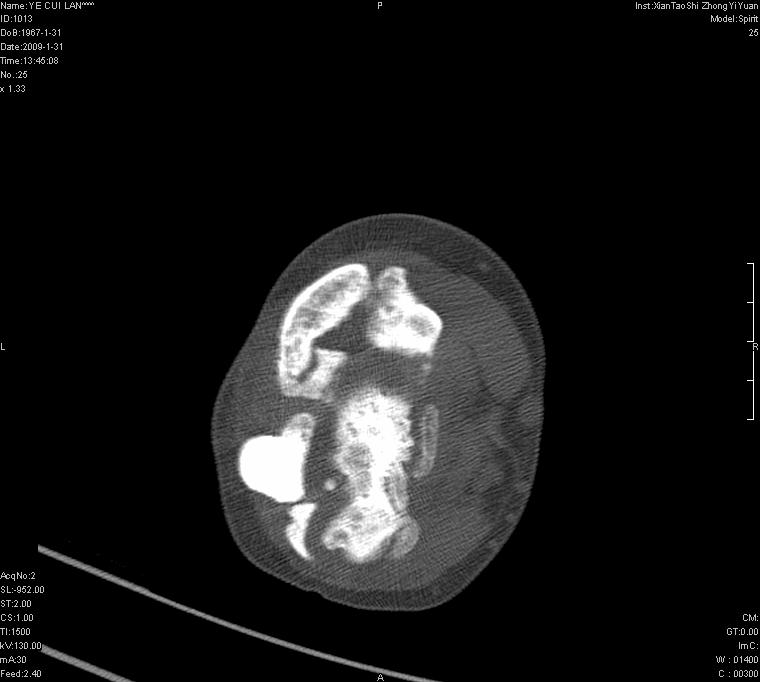

以下是引用王明发在2009-2-9 11:53:00的发言:[br]支持夏科氏关节,必要时行脊髓mri检查 [br]夏科氏关节是指由于某些神经系统疾病引起的关节病变,也被称为神经性关节炎。常见病因有脊髓痨、脊髓空洞症等。原发的神经病变可以造成关节深部感觉障碍,对于关节的震荡、磨损、挤压、劳倦不能察觉因而也不能自主地保护和避免,而神经营养障碍又可使修复能力低下,使病人在无感觉状态下造成了关节软骨的磨损和破坏,关节囊和韧带松弛无力,易形成关节脱位和连枷关节。关节面的破坏和骨赘的脱落变成关节内游离体。关节外形饱满肿胀,内有出血和渗出。这种病早期并无疼痛,不易被病人重视,仅表现为关节肿胀、无力、活动过度、动摇不稳。关节肿胀、无痛、活动范围超常是本病的重要特征。x光片可见有关节骨端广泛破坏、硬化或呈奇异形态,骨赘形成,关节间隙不规则或增宽,周围软组织钙化、关节内游离体、骨碎片等。结合x光片及临床症状,病人又有神经系统原发病症,即可确诊

以下是引用hhcckk在2009-2-9 14:31:00的发言:[br]夏科关节的六大表现[br]1.关节软组织肿胀。[br]2.关节的脱位与半脱位。[br]3.关节内的游离体。[br]4.关节面硬化,新骨形成。[br]5.骨质萎缩与破坏。[br]6.关节结构的紊乱。[br]加上患者无明显疼痛,诊断的把握性比较大